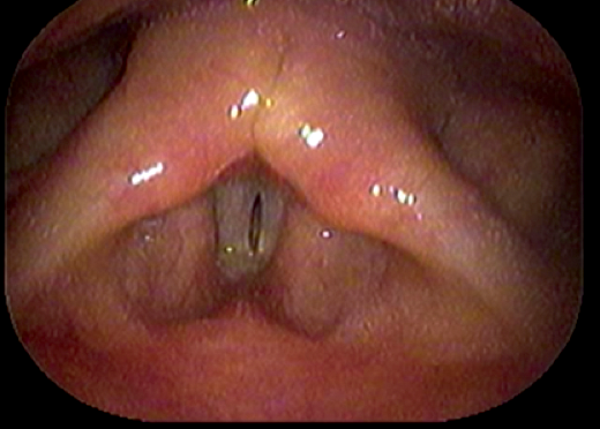

Short-term complications include perforation of the inner perichondrium and asymmetric laryngofissure. In the long-term, implant infection is rare. Hoarse voice or breathy voice can occur as well as recurrence of symptoms in about 10 % of cases. Revision surgery is rare. If it is required, this is usually due to breathy voice from a too wide titanium bridge. The long-term outcomes of this procedure are good. Figure 19 shows the vocal cords before and after surgery.

Figure 19: top 2 pictures) Before adduction, bottom 2 pictures) after adduction.